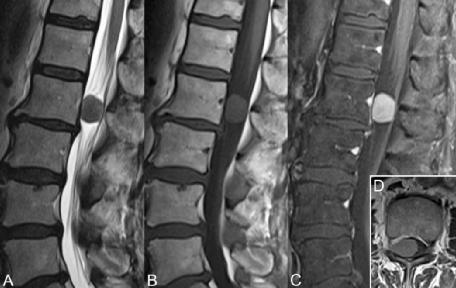

▲ 图51.2

图51.2 A-C (T2,T1,CE T1WI)显示,1型神经纤维瘤病患者L2椎体后缘有一神经纤维瘤,神经孔变宽。根据此处提供的插图,该病变可能代表神经鞘瘤或神经纤维瘤,然而,在该病例中,观察到两个额外的增强鞘内病变,支持后者。尽管在T2WI上可以看到囊性变性(A)为中央高信号区,但更具特征性的表现(脊柱神经纤维瘤)是T2WI上的靶样结构,低信号中心周围有稍高信号。该部位的神经源性肿瘤可通过造影增强与椎间孔椎间盘突出区分。丛状神经瘤(1型神经纤维瘤病的病理特征)偶见,累及骶丛,呈粗大的分叶状强化肿块。脊膜瘤是与髓外硬膜下肿块的进一步鉴别诊断。与颈椎不同,这些病变往往累及胸腰段椎管的后外侧。图51.3 A-C中病变上方和下方的加宽蛛网膜下腔将其定位于髓外硬膜下。与上述病变一样,该脊膜瘤在增强前T2 (A)和T1WI (B)图像上表现出与脊髓等信号强度,前者在高信号 脑脊液下最明显。(C)增强显示由于肿瘤血管形成而具有特征性的显著、均匀增强。偶尔,在FSE T2WI上,沿血管特别丰富的脊膜瘤周围可见血流空洞。致密钙化也很常见,在所有成像序列中均显示低信号。图51.3 D的轴位图像显示该脊膜瘤延伸至孔内。

▲ 图51.3